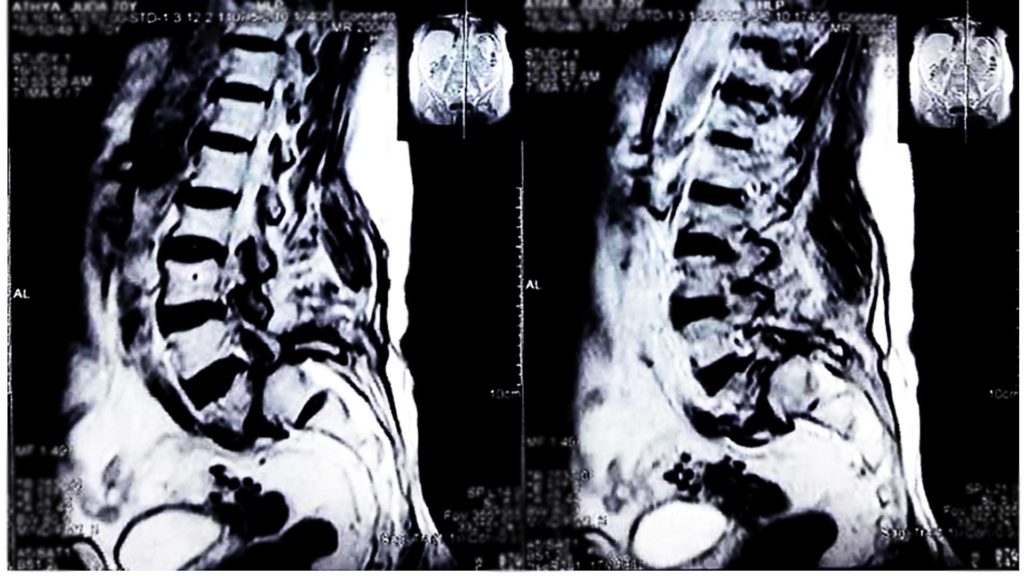

Bel ağrısı şikayetiyle hasta hekime başvurduğunda ayrıntılı olarak anamnez alınır ve ardından fizik muayene yapılır. Hekimin isteği üzerine yapılan radyolojik görüntüleme ile bel kayması teşhisi koyulur. Bel kayması türüne ve şikayetlere göre tedavi düzenlenir. Bazı vakalarda istirahat etmek ya da karın ve sırt kaslarını güçlendiren egzersiz programları tedavi için yeterli olabilir. Bel kaymasının şiddetine bağlı olarak hekim, hastayı fizik tedavi ve rehabilitasyon bölümüne yönlendirerek, kendisine özel bir program oluşturulmasını önerebilir. İlaçla tedavi de bir diğer seçenektir. İlerlemiş vakalarda ise omurganın eski yapısına kavuşması için cerrahi operasyon gerekir. Bel kayması tedavisi amacıyla yapılan operasyon sayesinde baskılanan ve bel kayması şikayetlerine neden olan sinirler rahatlatılarak, omurga sabitlenir. Eğer sizin de bel ağrısı şikayetiniz varsa, sağlık kontrollerinizi yaptırmayı ihmal etmeyin.